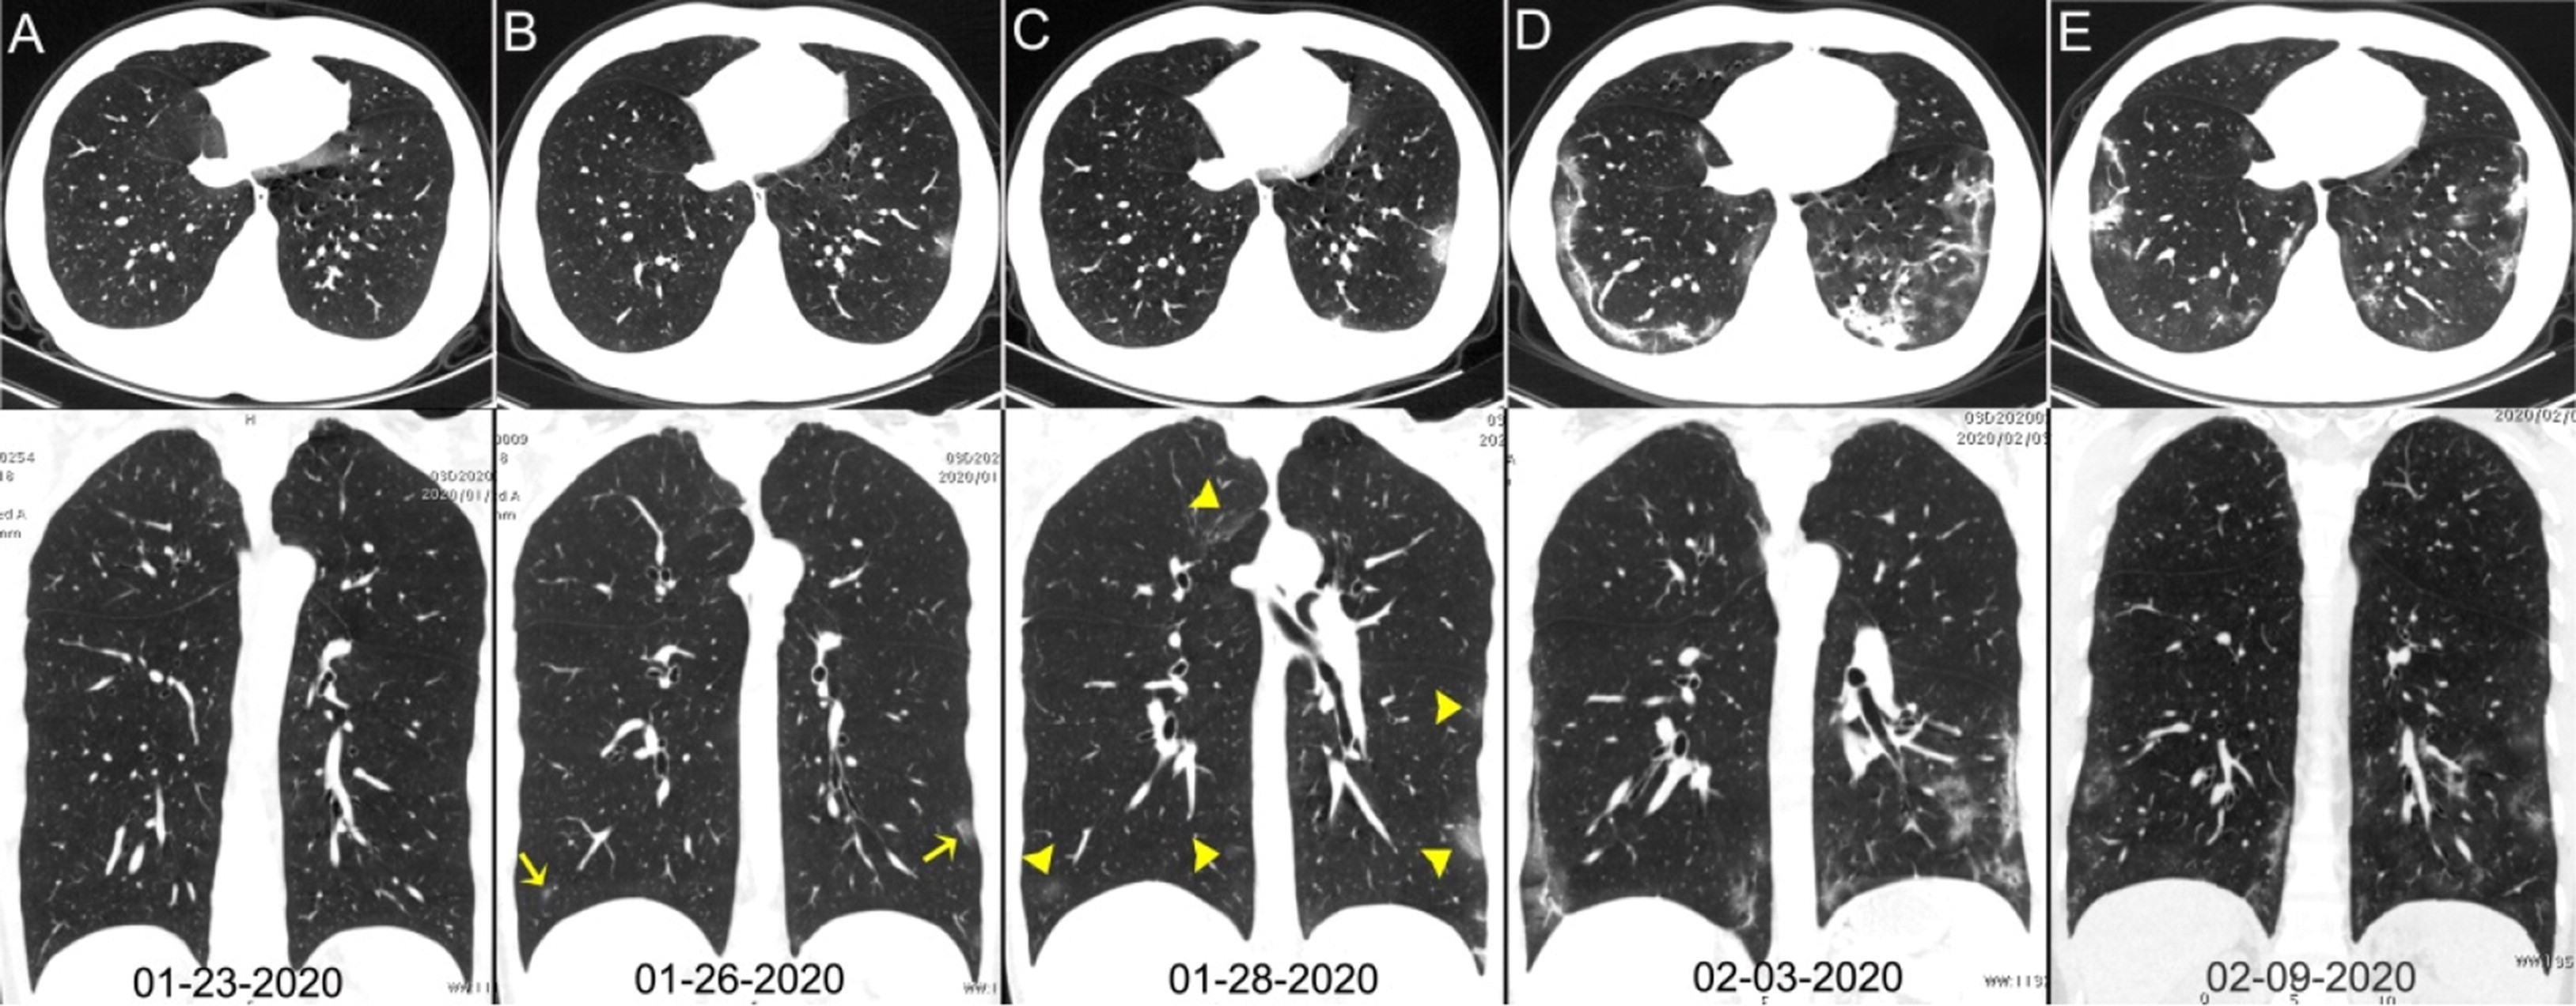

Поражение легких является одним из основных симптомов коронавируса (COVID-19). В данной статье представлены фото рентгеновских снимков, которые позволяют визуально оценить состояние легких при этом заболевании.

Фото рентгеновских снимков поражения легких при COVID-19

На фотографиях рентгеновских снимков видно, как вирус воздействует на легочную ткань. Характерные признаки поражения легких включают пятна, инфильтраты и наличие жидкости внутри легочных альвеол.

Фото рентгеновских снимков помогают врачам и специалистам визуально определить степень поражения легких и принять соответствующие меры лечения и поддержки пациента.